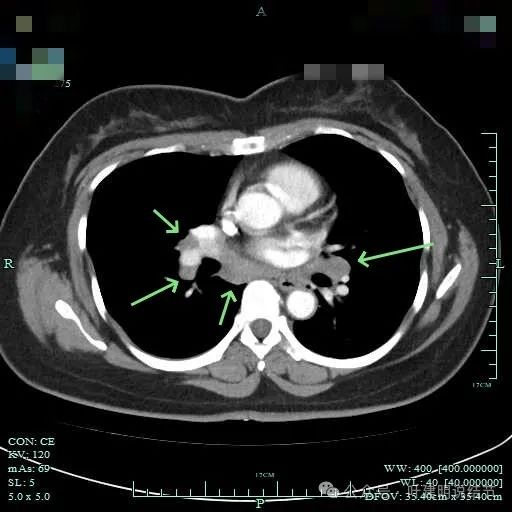

双侧肺门与纵隔明显肿大淋巴结。

右侧腔静脉旁肿大淋巴结。

右侧肺门与纵隔肿大淋巴结

胸部CT增强报告示:两肺多发结节,其中右上叶尖段结节肿瘤性病变考虑,伴肺门及纵隔多发淋巴结转移考虑。